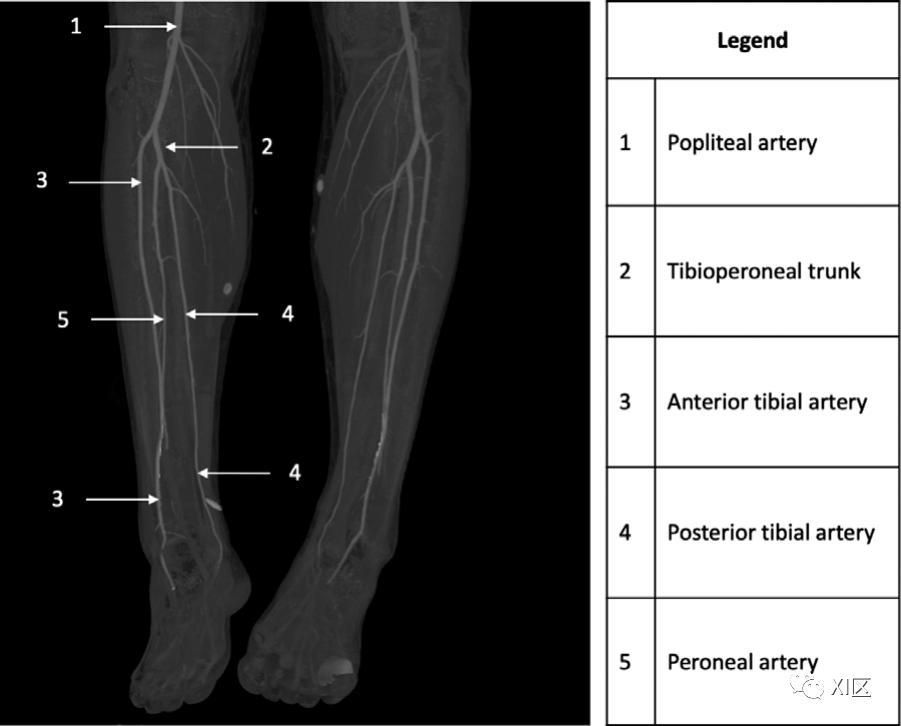

腘动脉的平均直径为5.9-6.2mm,沿大腿后侧下降,是供应膝关节的膝关节分支的起源。最常见的是,在胫腓关节水平,腘动脉分叉为胫前动脉和胫腓干。出于干预的目的,腘动脉可分为三段。P1段从髁间窝到髌骨近端/上缘,P2段从髌骨近端到膝关节中心,P3段从膝关节中心到胫前动脉的起源(图2)。胫前动脉在前方穿过胫骨和腓骨之间的骨间膜。胫腓干进一步分为胫后动脉(直径为2.0-2.2mm)和腓动脉,两者都供应腿部后部。

图2 31岁,解剖结构正常。冠状位上膝关节下方的最大密度投影CTA图像显示腘动脉(1)分叉成胫腓干(2)和胫前动脉(3)。胫腓干进一步分为胫后动脉(4)和腓动脉(5)。据报道,11.3%的患者在CTA上看到腘动脉的分支模式变异。腘动脉分支最常见的变异是胫前动脉的高位起源(图3),胫前动脉和腓动脉的共同起源(图4),所有三个分支都在5mm内分叉的三叉,以及胫后动脉发育不良或再生不良。腓动脉在踝部终止于由前部和后部穿孔分支形成的分叉处。95%的人胫前动脉和胫后动脉继续进入足部。5%的人存在一个变异,就是没有这些径流血管之一,而有一个腓动脉可能继续到足部。